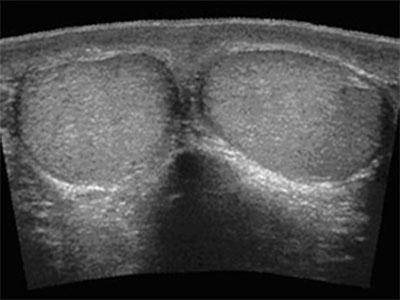

Для дооперационной диагностики применяют метод диафаноскопии – просвечивание мошонки обыкновенным фонариком. Если у больного возник перекрут гидатиды яичка, то при просвечивании в верхней части мошонки будет видно небольшое бобовидное образование темного цвета – это и есть воспаленное образование.Характерные симптомы перекрута являются основанием для проведения УЗИ диагностики. Такое исследование позволяет точно определить локализацию воспаленной гидатиты.

- трансректальное УЗИ,

- диафаноскопия,

- анализ мочи (для исключения инфекции).

Если поставить диагноз затруднительно, может быть назначено радионуклидное сканирование. Благодаря этому методу исследования можно выяснить степень недостаточности снабжения яичек кровью.